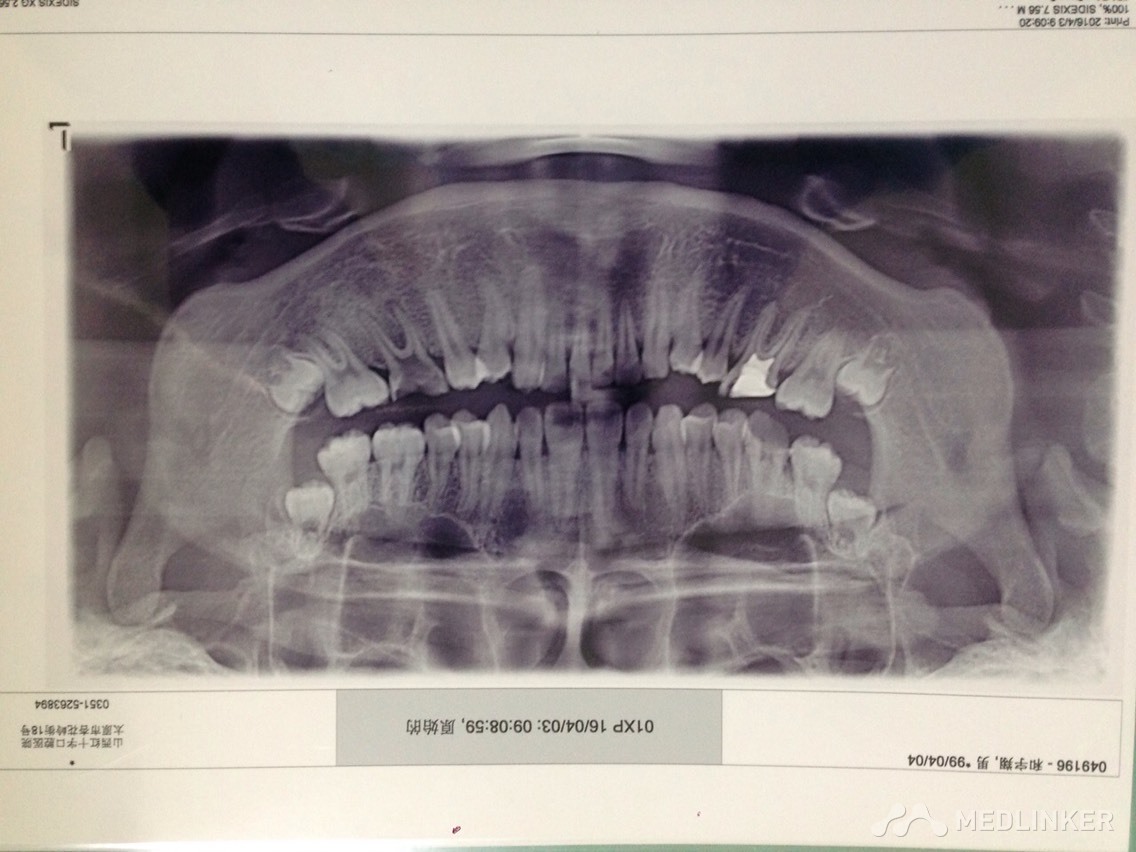

患者男,17岁,上前牙不美观要求矫正

各位同仁帮忙看下这个患者适合怎么矫正?

各位同仁帮忙矫正的方案是怎么样?